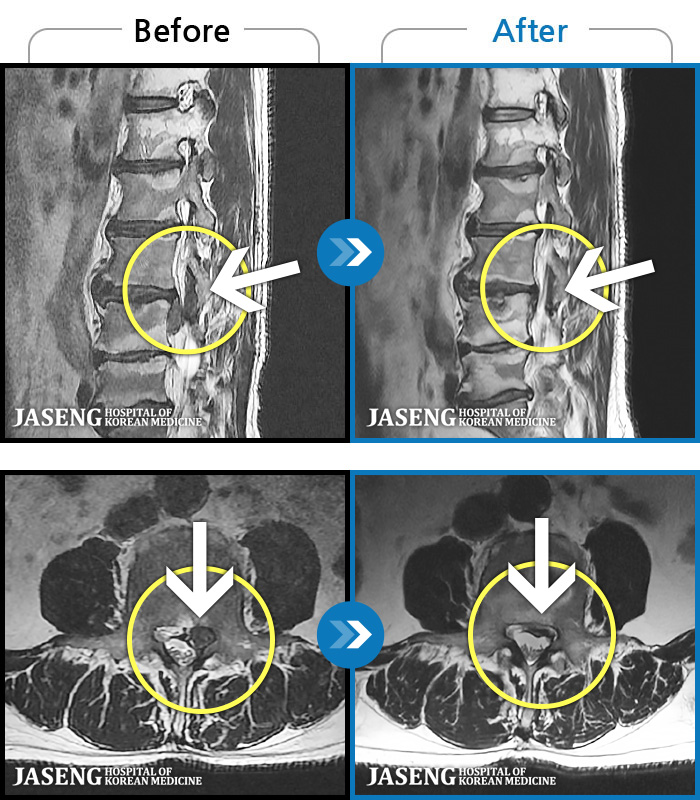

- MRI ġ

MRI ġ

1,237 MRI ũ ʸ Ȯϼ.

㸮 ϻ .